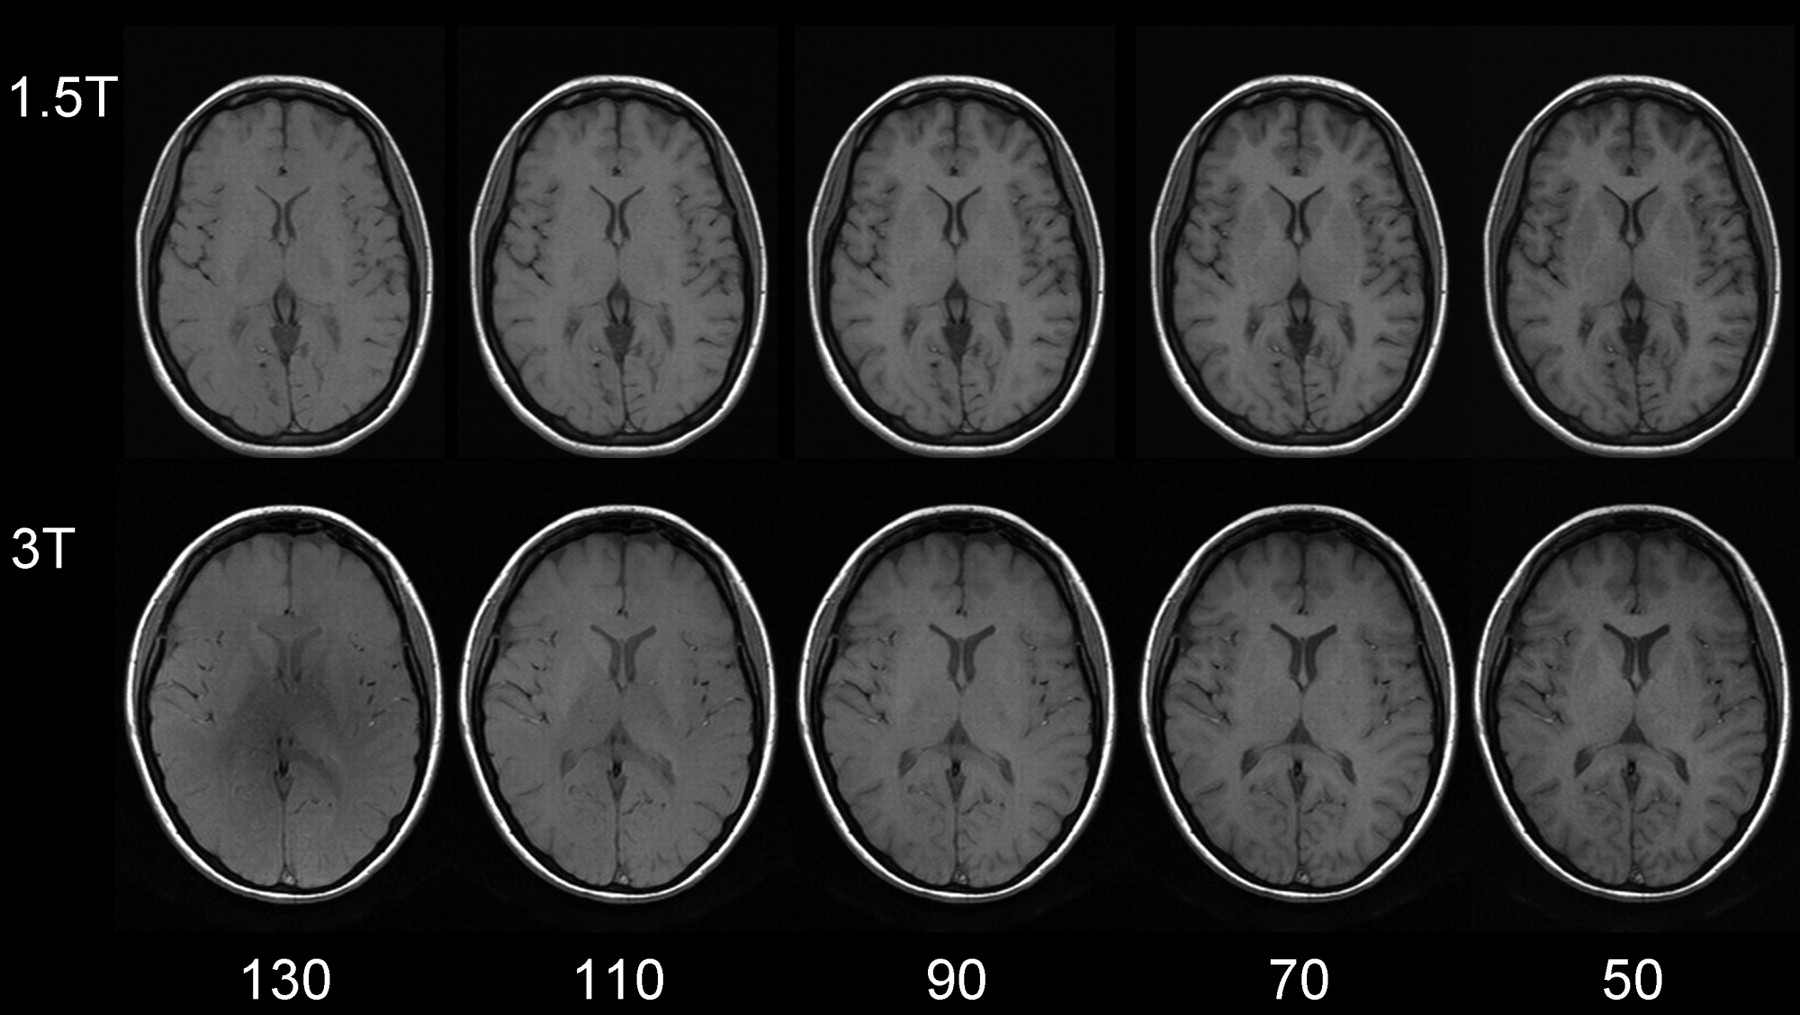

Apparently, gray-to-white matter contrast is reduced in spin-echo T1 imaging at 3T (30) when compared with 1.5T (Fig 6). There are several factors contributing to this observation. T1 times of gray and white matter lengthen and converge at higher fields (31–33). Moreover, shielding effects induced by eddy currents prevent central parts of the image from being properly excited (16), which results in reduced signal intensity of the basal ganglia region. In addition, magnetization transfer effects are enhanced at higher B0, thus reducing signal intensity and contrast. There are several ways to compensate for these effects. For example, inversion recovery sequences appear very well suited if one is only interested in increasing gray to white matter contrast (Fig 7). The inversion pulse, however, interferes with visualization of contrast enhancement following gadolinium administration. Enhancing lesions may not be visible (Fig 8), because in inversion recovery sequences, unlike conventional T1 spin-echo sequences, the tissue with the shortest T1 does not necessarily exhibit the brightest signal intensity, depending on T1. Therefore, inversion recovery sequences are not quite useful for comparative pre- and postcontrast T1 spin-echo imaging, regardless of B0. A different approach to increase gray-to-white matter contrast during T1-weighted spin-echo imaging at both field strengths is to reduce the excitation flip angle (34). Although this reduces SNR slightly, the gain in gray-to-white matter contrast is obvious and more pronounced at 3T (Fig 9). The effect can be predicted from theoretical calculations (35) by using known T1 and T2 relaxation times of gray and white matter (33) but is empirically larger than the theoretical predictions at 3T, probably because of shielding and magnetization transfer effects (34).

Same section position with spin-echo T1-weighted sequences at 1.5T (upper row: TR, 700 ms; TE, 10 ms; section thickness, 5 mm; matrix, 256 × 192; FOV, 220 × 220 mm2; bandwidth, 200 Hz/pixel) and 3T (lower row: same imaging parameters). Flip angles decreasing from left to right 130°, 110°, 90°, 70°, 50°. The lowest flip angle shows the best gray-to-white matter contrast. The effect is stronger at higher field.